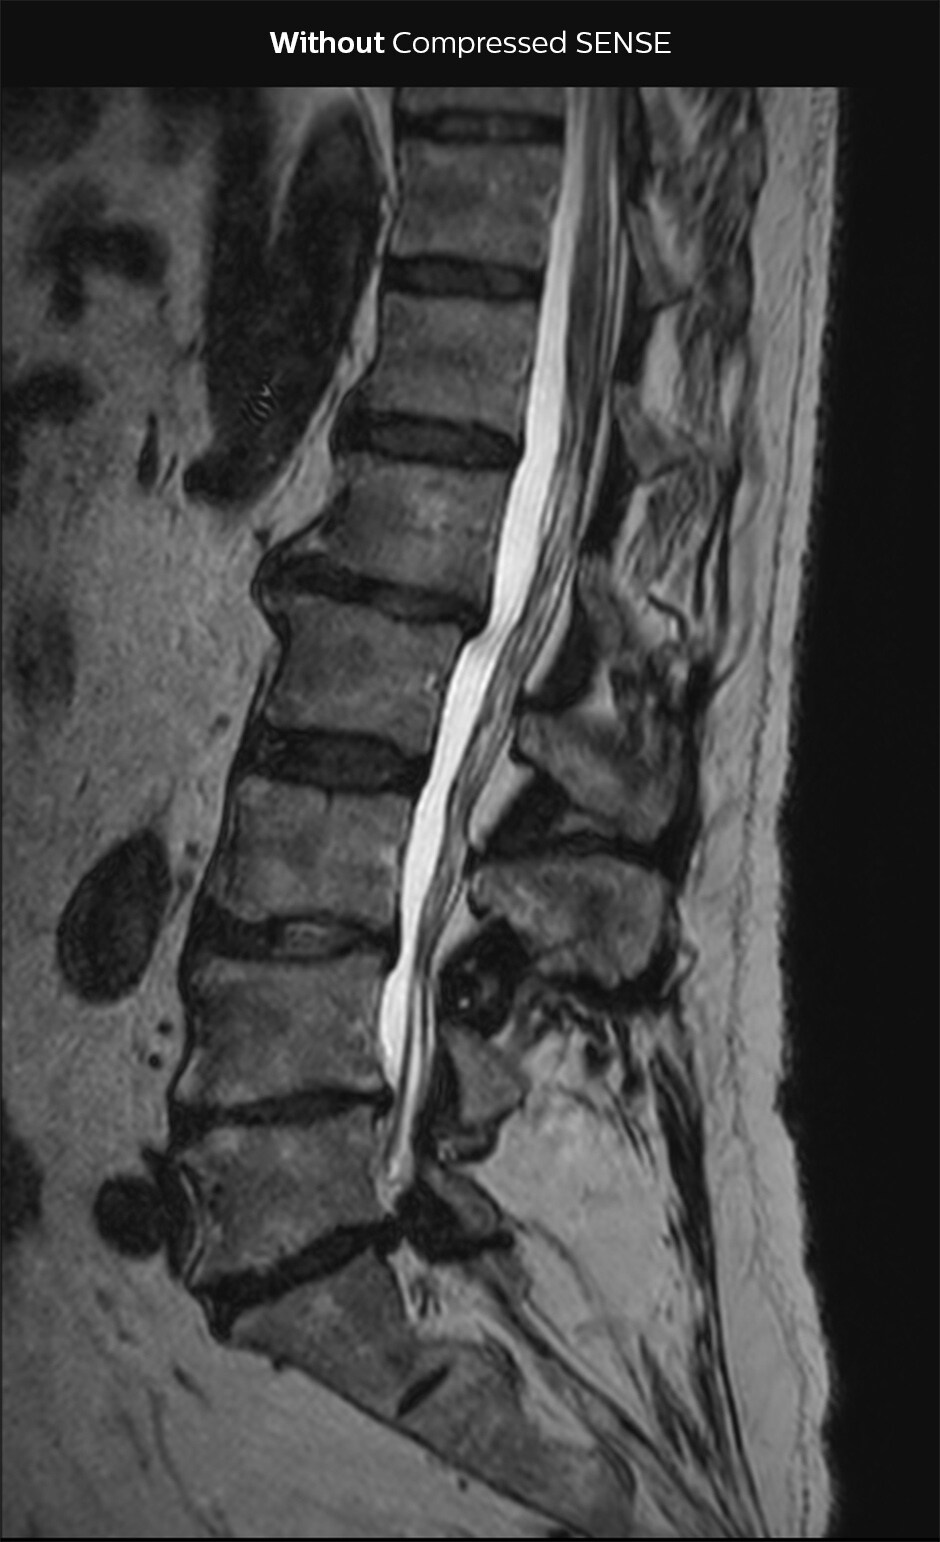

“Our aim for the spine is to use Compressed SENSE to help us make the switch to using 3D SpineVIEW. In lumbar spine, for example, we can reduce scan time for 3D T2W SpineVIEW by 27% to 4:46 minutes, voxel size 0.8 x 0.8 x 1 mm."

In this example Compressed SENSE has a 26% shorter scan time and improved spatial resolution simultaneously.

3D T2 SpineVIEW, scan time 6:29 min, voxel size 1 x 1 x 1.4 mm

3D T2 SpineVIEW, scan time: 4:46 min, voxel size 0.8 x 0.8 x 1 mm

In some cases, Dr. Sartoretti also sees the benefit of keeping the acquisition time the same, and increase the amount of detail in images. “In nerve imaging, for example of plexus and in peripheral neurography, more detail is helpful to see the tiny nerves. We also like to add Compressed SENSE to the 3D T1 Black Blood sequence, for obtaining higher resolution when looking at the detailed anatomy of vessel walls and to visualize pathology of these tiny vessels in the brain.” The lumbar spine example above also illustrates an improvement of spatial resolution with use of Compressed SENSE.